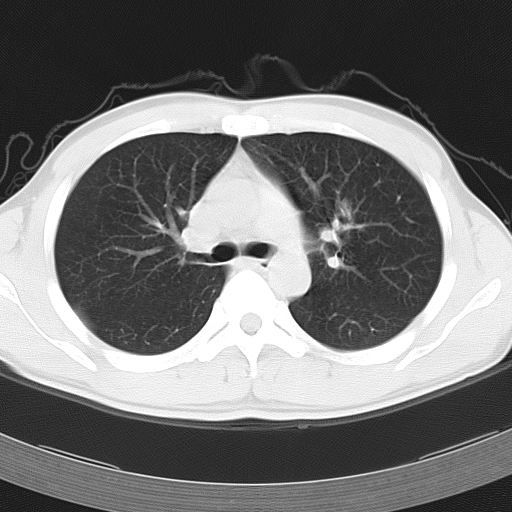

男,34岁,咳嗽2~3个月,无咳血,病初有发热。

两上肺磨玻璃样改变,均位于肺外周,考虑1、肺泡蛋白沉着症?2、肺泡炎?请询问有无养鸟史 3、脱屑性间质性肺炎?建议进一步检查、复查随访

两上肺的ggo,靠近胸膜,不是以节段分布,青年男性,个人意见为吸入性的真菌感染可能为大------------呼吸内科医生

两肺上叶近胸膜磨玻璃样阴影,考虑1、炎性病变。 。2、过敏性炎症?

病灶特点:

分布在肺野的外带,病灶边缘清楚,病灶以磨玻璃影为主夹杂少许纤维状高密度影

支持zhangzhongshou主任,考虑蛋白沉着症可能性大

(1)斑片状磨玻璃影:指肺野密度朦胧增加,内可见肺血管纹理影,系肺泡腔内充满低密度的磷脂蛋白物质所致。

(2)其内部小叶间隔或小叶内间隔增厚所形成的网格状影,为小叶间隔水肿、肺泡壁内淋巴细胞和巨噬细胞浸润以及小叶内淋巴管扩张的缘故。

(3)病灶边缘清楚,呈地图样分布于肺野外围或肺门及中央区。

病变分布以双上肺叶外带明显,双下肺未见异常,此一点不十分支持肺泡蛋白质沉着症,病变未见铺碎路石征,也不肺泡蛋白质沉着症。考虑间质性肺炎,结核不除外。

肺泡蛋白沉积症;胸膜下区磨玻璃样,实变区见纹理走形,地图样改变。做mri。

文献报告:x线表现 (1)中央型:肺内弥漫细小模糊结节或羽毛状浸润阴影。其内可见空气支气管征,病变自两肺门向外围延伸分布,形成蝶翼状外貌,甚似肺泡性肺水肿,为本病典型表现。(2)外围型:小叶浸润病变分布于两肺外围或一侧外围,轮廓模糊。

ct表现 (1)中央型:表现为蝶翼状浸润性阴影对称分布于两侧肺门周围,其内可见支气管充气征,病变区与正常肺组织分界清楚。(2)外围型:表现为多发性条片状、斑片状及斑块状高密度影,弥散、对称或不对称分布于两肺或一侧肺外围部位。病变区与正常肺组织及脏层胸膜面分界清晰,呈地图样改变。hrct可显示小叶间隔增厚及肺小叶内淡淡的密度增高影等细微结构,同时易发现肺大疱、肺气囊及节段性肺不张。

再仔细阅读该病人的ct片,我们不难发现,病例所表现的正是外围型的肺泡蛋白沉积症表现,即:为多发性条片状、斑片状及斑块状高密度影,弥散、对称或不对称分布于两肺或一侧肺外围部位。病变区与正常肺组织及脏层胸膜面分界清晰,呈地图样改变。